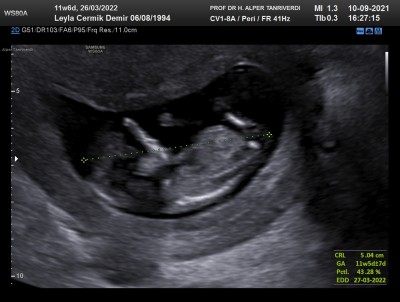

11hafta +6 günlüktü burda. Artık tamamen bi insan gibi her şeyi oluşuyor cinsiyetinide göstermişti bize. :) şimdi 15 hafta olucaz.

Maşallah canım cinsiyyət ne inşallah bende de oyle olur

Saol canım erkek dedi doktorumuz